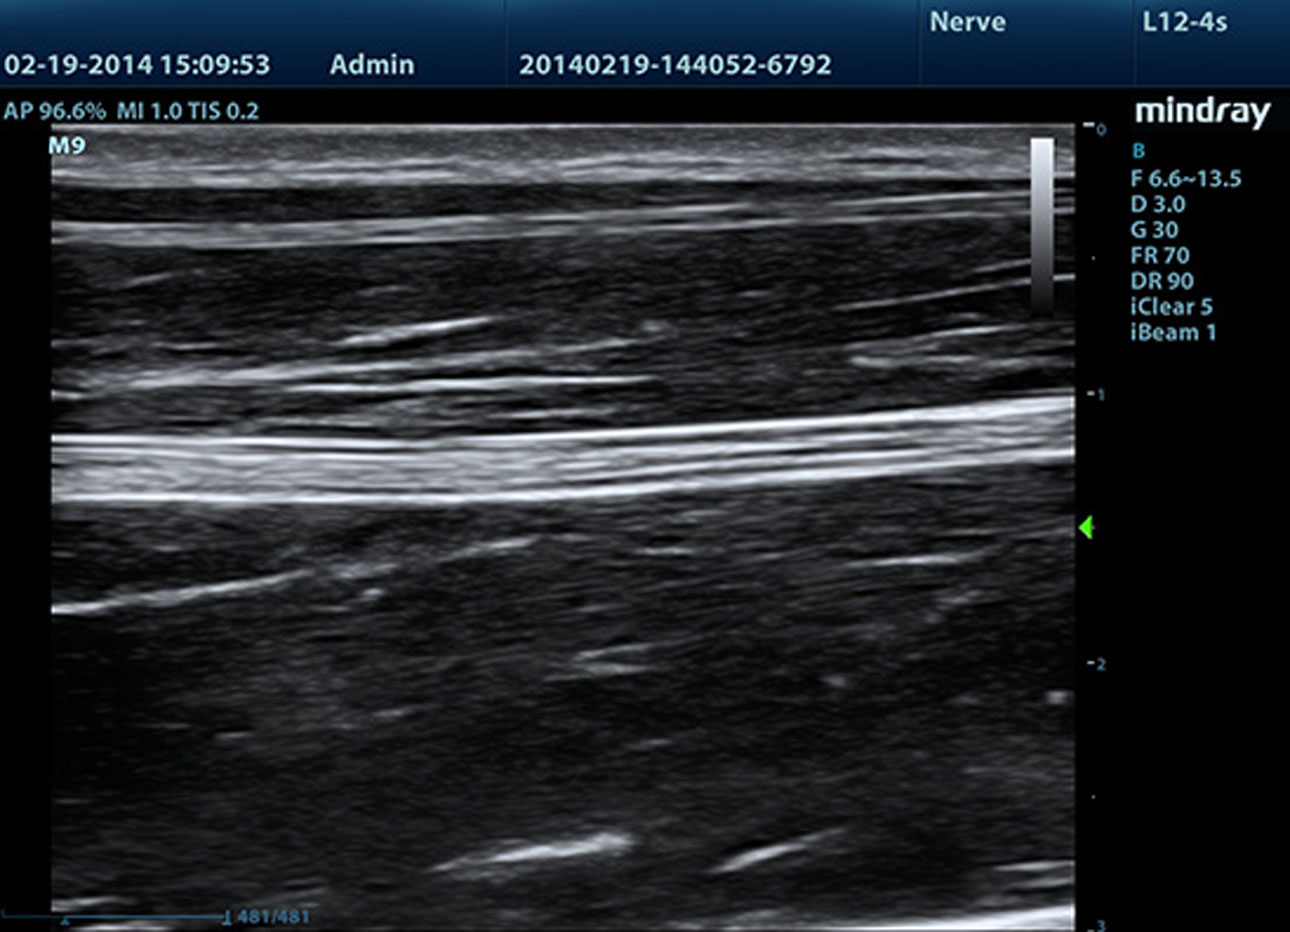

iNeedle?(Needle Enhancement Visualization)

Advanced needle visualization allows the needle increased visibility even during steep-angled procedures, while maintaining superior image quality. Improved confirmation of needle location in tissue minimizes harm to surrounding tissue.